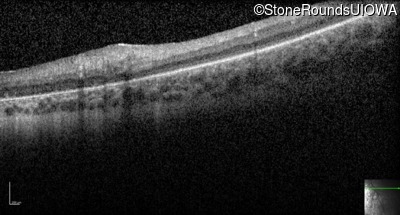

Optical Coherence Tomography - Right -

No Light Perception

Optical Coherence Tomography - Left -